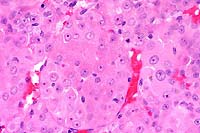

20x

obj

40x

- Case 13-2. Testis. Neoplastic polygonal cells with

brightly eosinophilic globular cytoplasm form pockets & nests.

obj, PAS

- Case 13-2. Testis. Packeted polygonal tumor cells

rarely contain globular PAS positive cytoplasmic material.

- AFIP Diagnosis: Testis: Interstitial (Leydig) cell

tumor, malignant, Long Evans rat, rodent.

- Conference Note: Conference participants had great

difficulty with this case. While the majority agreed with the

contributor's diagnosis of malignant seminoma, several favored

malignant interstitial (Leydig) cell tumor. An unencapsulated,

lobulated, densely cellular neoplasm with multifocal to coalescing

areas of necrosis replaces most of the testicular parenchyma.

The neoplasm is composed of polygonal to elongate cells arranged

in nests, packets, and variably broad cords supported by a fine

to moderate fibrovascular stroma. A key histological feature

present in some sections is packets and lobules of large polygonal

cells that have abundant, brightly eosinophilic, granular to

globular cytoplasm and round, centrally placed nuclei with prominent

nucleoli; these cells are interpreted as neoplastic Leydig cells.

Cells with features intermediate between the Leydig-like cells

and the poorly differentiated cells are also present.